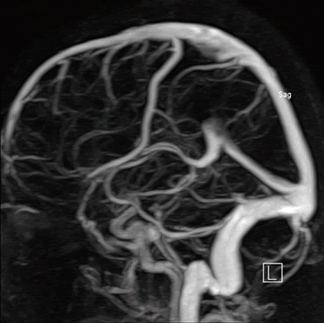

Данные МР-веносинусографии соответствуют результатам рентгеноконтрастной ангиографии и спиральной КТ-ангиографии [26]. В соответствии с феноменами in-flow (во время потока) и phase-shift (фазового сдвига), влияющими на МР-сигнал, существуют два принципиально разных способа получения изображений: time-of-flight (времяпролетное TOF) и phase-contrast (фазо-контрастное PS) соответственно. При выявлении аномалий синусов ТМО обязательно оцениваются синусы на контрлатеральной стороне в качестве основного источника компенсации. При тромбозе синусов ТМО наблюдается отсутствие сигнала кровотока. Ультразвуковые технологии позволяют также визуализировать и оценивать количественные параметры кровотока по МВ и ВС. Признаком тромбоза верхнего сагиттального синуса является увеличение скорости кровотока по базальным венам и прямому синусу. При тромбозе прямого синуса или синусного стока регистрируется ретроградный кровоток по базальным венам [27]. У пациентов с тромбозом поперечного синуса при транскраниальном дуплексном сканировании выявляется асимметричный кровоток или отмечается отсутствие сигнала кровотока, что может соответствовать гипоплазии поперечного синуса или его тромбозу [28].

Диагностика магнитно-резонансная ангиография сосудов головного мозга производится при подозрении на тромбофлебит сигмовидного синуса.

- МРТ ангиографии сосудов головного мозга с контрастированием